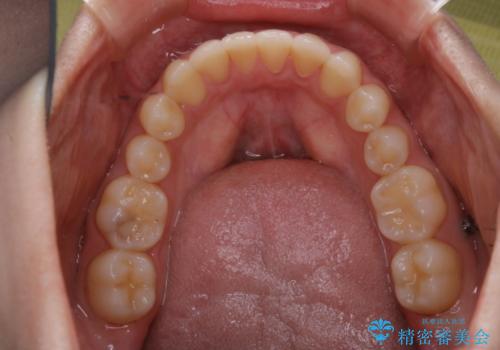

矯正治療終了後にPMTC(Professional Mechanical Tooth Cleaning)

- 矯正治療が終了したため、クリーニングでもきれいにしたいとのことでした。PMTC60分コースを行いました。

矯正治療が終わり、せっかくきれいになった歯並びも、虫歯・歯周病などになってしまっては元も子もありません。

矯正治療やセラミックなどによる被せ物の治療終了のタイミングではクリーニングを行い、汚れや着色の除去、歯と歯の間・歯と歯肉との境目などのケアをしっかりすることをおすすめしています。

ご自身での歯ブラシ・セルフケアを行うと同時に、定期的なクリーニング(PMTC)を行うことで、いつまでも健康な歯を保つことができます。